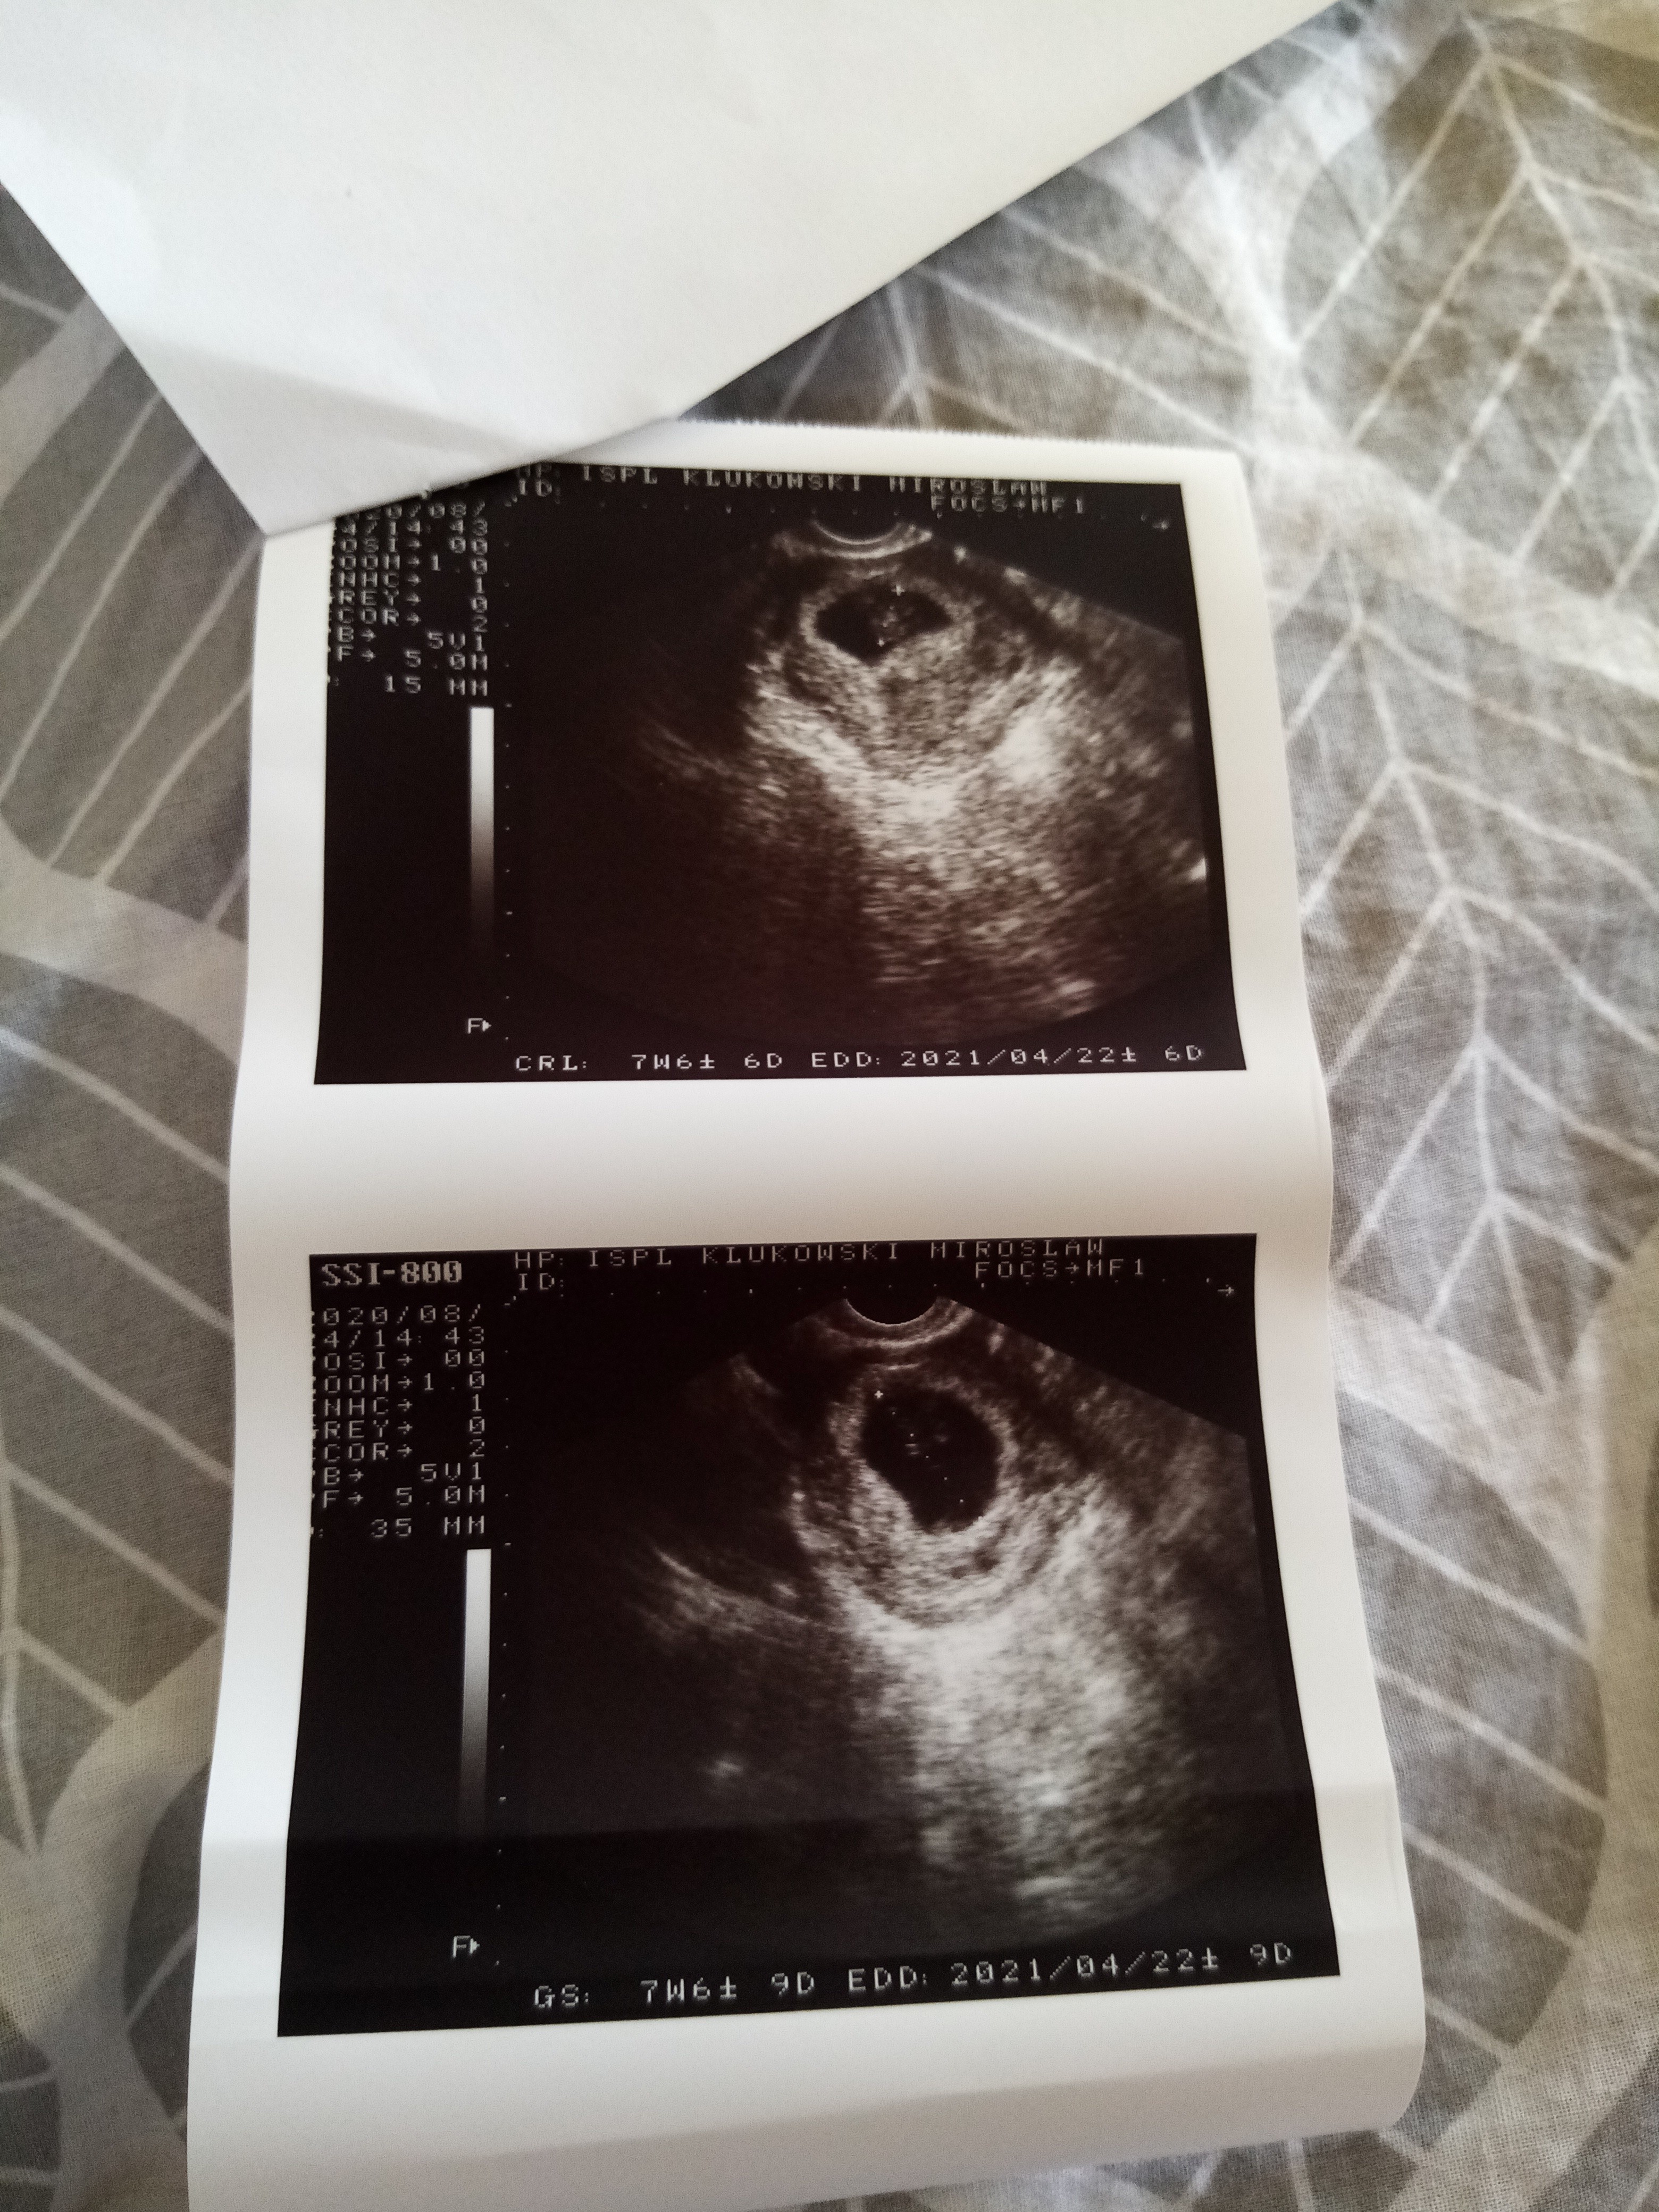

Właśnie też czekam w szoku na relacje, bo jak myślę o tym, to tak jakby ciąża przetrwała? Utkwiła mi ta historia w głowie, bo @Początkująca30 przeszla przez stratę pisała, że 3 tyg temu miała łyżeczkowanie i nie dostała jeszcze @,a że źle się czula (ból piersi o ile pamiętam) to zrobiła test i wyszedł pozytyw, potem beta i to mega wysoka i dziś to zdj z usg 😮 tam na dole jest oznaczenie, że to prawie 8 tydzień 😮 dlatego pytam jak się czuje, bo ja bym była zszokowana